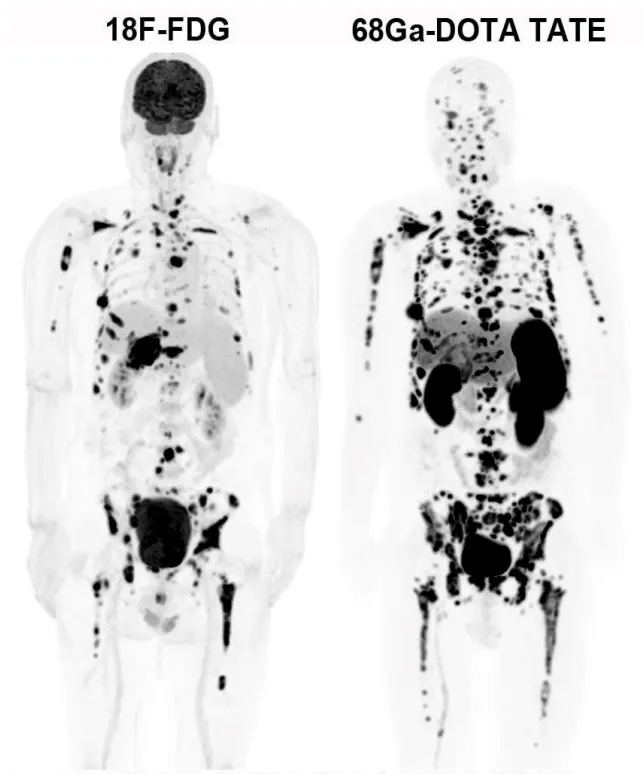

68Ga-PET/CT是一种更先进的癌症检查方法,比传统的“糖代谢”检查(18F-FDG PET/CT)更精准,尤其适合那些不太吸收糖分的肿瘤,比如某些神经内分泌瘤、前列腺癌等。68Ga-PET/CT就像“智能导弹”,能根据不同癌症的特点精准定位,比普通检查更准、更靠谱!

3.神经内分泌肿瘤检查(68Ga-DOTATATE):专门针对神经内分泌肿瘤(比如某些胃肠胰肿瘤、类癌等),能准确找到肿瘤位置,判断严重程度和治疗效果。

△神经内分泌癌骨骼多发转移